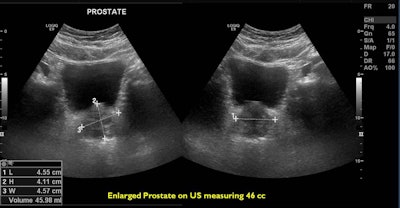

As men age, the prostate gland grows larger and may begin to press on the urethra. Enlarged prostate affects more than half of men by age 60 and causes symptoms such as frequent urination, weak urine stream, and a persistent feeling of having to urinate. Surgery is the standard treatment for the condition, but it can cause complications such as sexual dysfunction.

Prostate artery embolization is a noninvasive procedure that can bring long-term relief from symptoms caused by an enlarged prostate. This procedure works by closing the blood supply to the prostate, and, as a result, the prostate shrinks in size, reducing blockages and improving the symptoms.

One of the most promising benefits of PAE has been its efficacy in a variety of patient populations. PAE has been performed in patients with both small and large prostates. TURP in larger gland sizes, especially with prostate volumes larger than 80 cm, is associated with longer operative times and an increased risk of bleeding and anesthesia-related complications. In contrast, PAE has been demonstrated to be safe and efficacious in varying prostate sizes with no major complications.